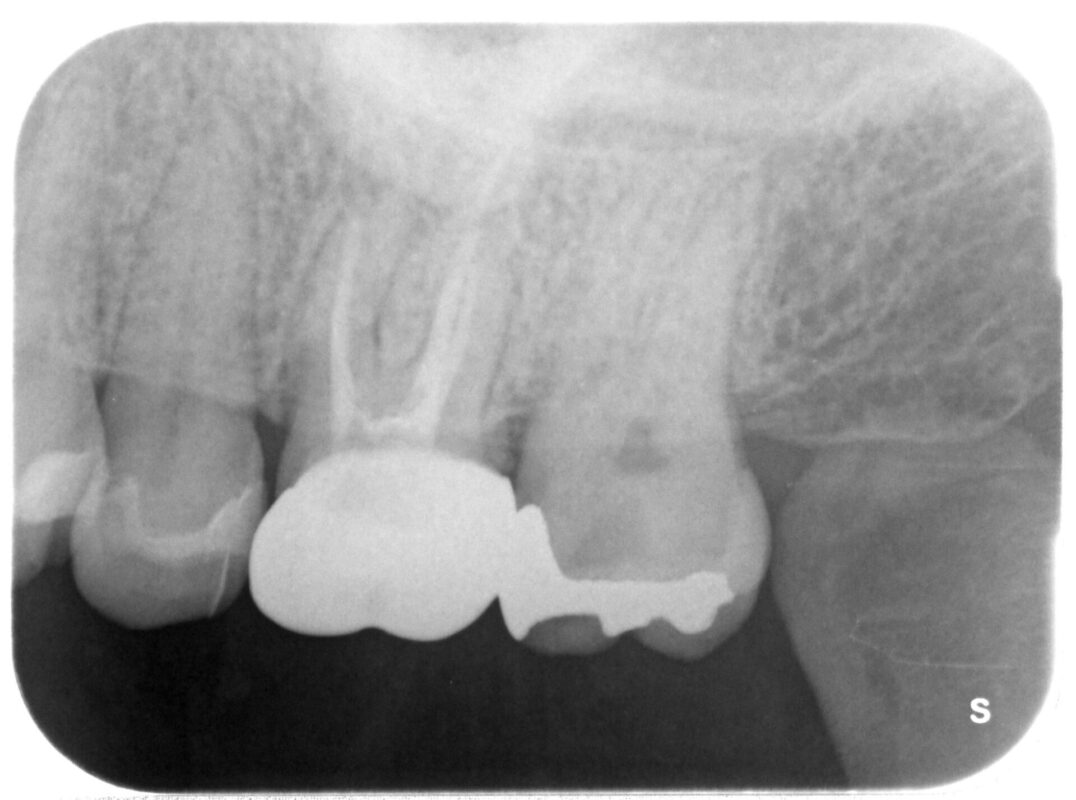

根管治療(充填後)

2回目の治療で痛みも完全に消失していたので、キッチリ根管充填行えました。

一部マイクロスコープ使用。

治療した左側の歯牙(┗6)に初診時からサイなストラクトが存在し(無論前医では指摘されず)、

患者さんも違和感、噛んだ時の鈍い痛みが前からあったとの事。

当院において術前に撮影したCTにより問題あることを確認していましたが、まず痛みのあった┗7の治

療を優先、その根管充填完了したので、今度は┗6部の対応としましたが、CTから歯根先端に大きな膿

の袋が確認でき、歯根破折を起こしているようでした。